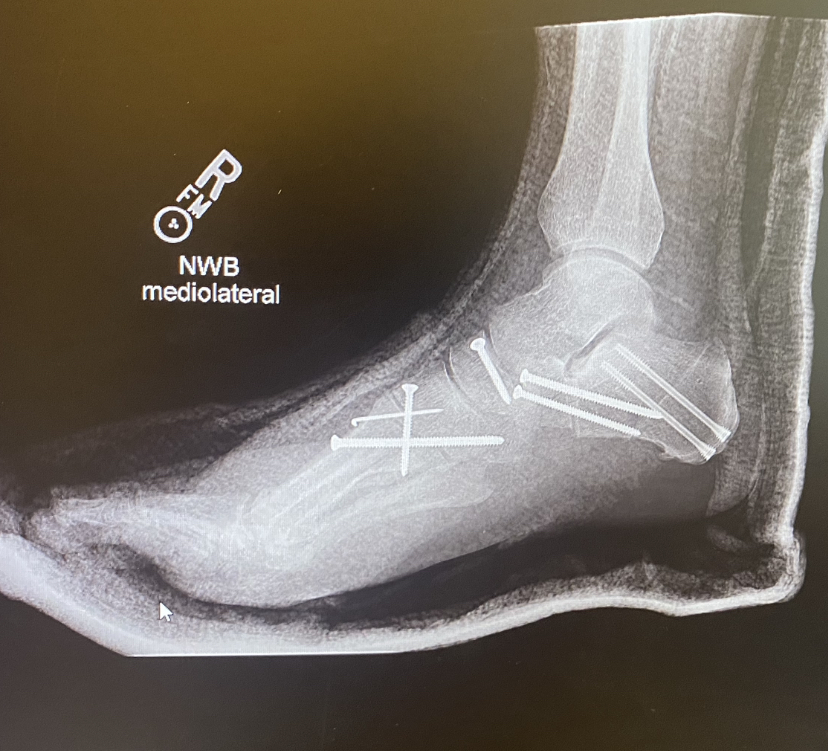

I’m happy because this week I started walking (limping) again.

Back in March, had major flat-foot reconstructive surgery. Nine hours in the operating room to do eleven procedures (bone grafts, tendon transfers and ligament repair)…it’s been a long non weight-bearing spring, summer and fall.

But being able to put one foot in front of the other this week has made me the happiest in quite a while.